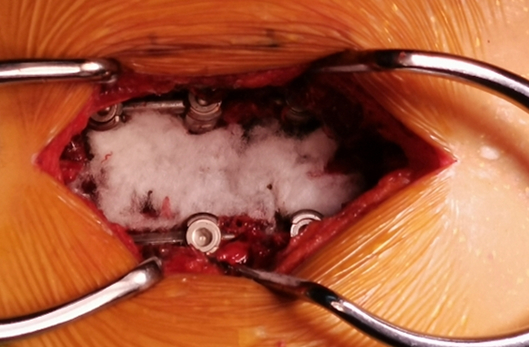

O臂术中定位辅助置钉

术中内固定置入

神经外科与脊柱外科联合手术